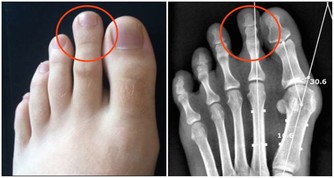

➀放屁很多且很臭:如果經常放屁,且很臭,頻率高到影響工作和生活,需警惕是否患上“潰瘍性結腸炎”等疾病。